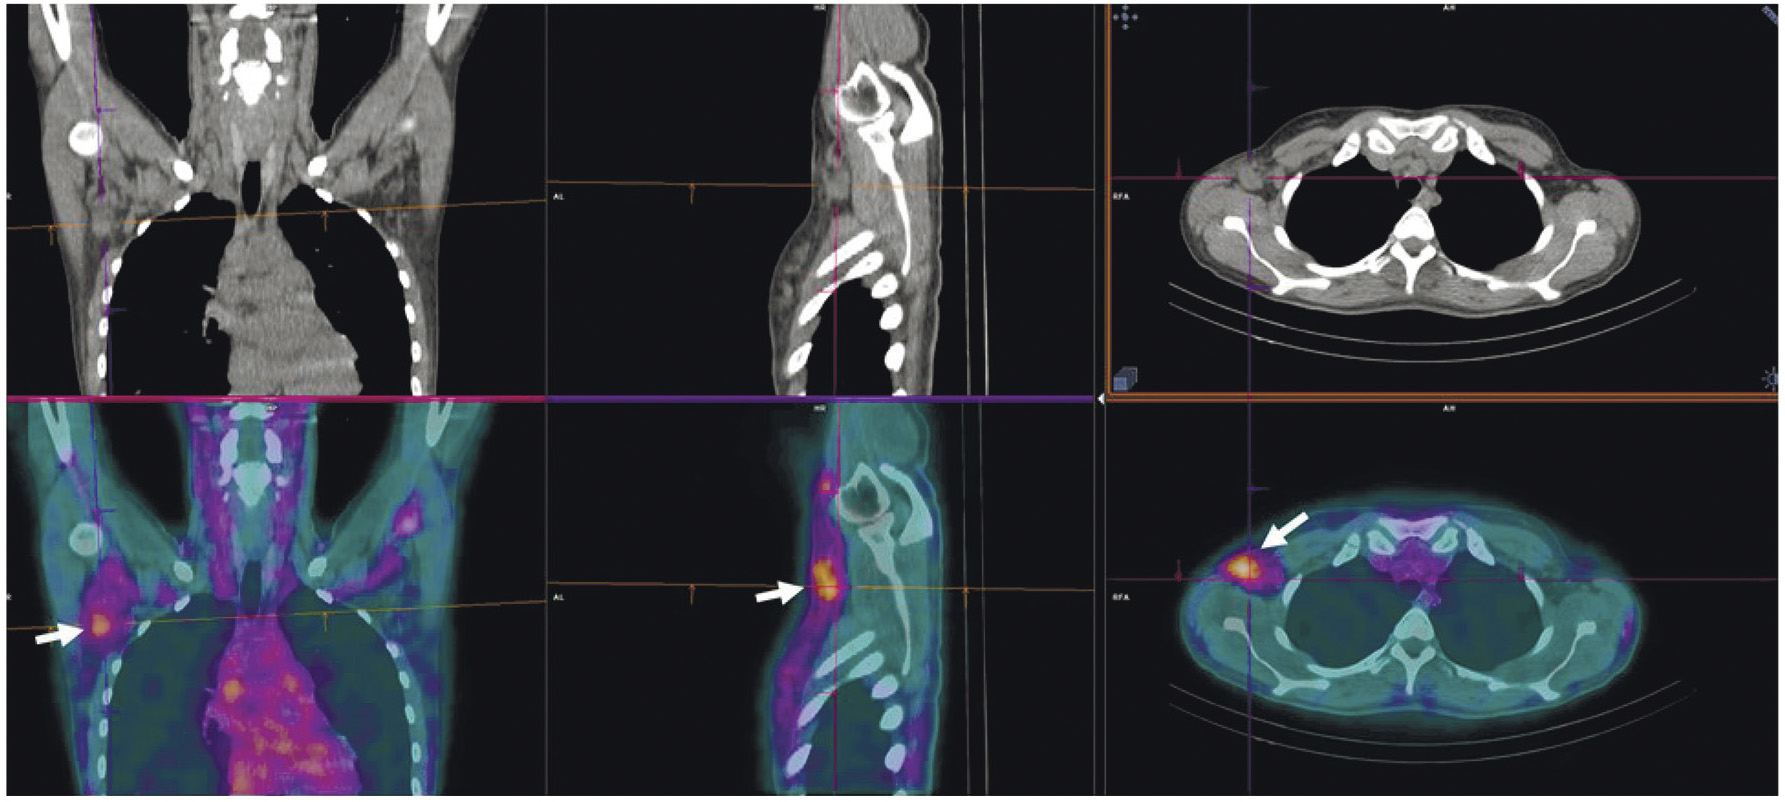

В рутинной клинической практике для ПЭТ/КТ-визуализации опухоли предстательной железы и её метастазов применяются радиофармпрепараты на основе простатспецифических мембранных антигенов, меченных 68Ga ([68Ga]Ga-ПСМА-11, [68Ga]Ga-ПСМА-617, [68Ga]Ga-ПСМА-I&T) либо 18F ([18F]F-DCFPyL, [18F]F-ПСМА-1007) [22, 23]. Главные преимущества меченных 99mТс препаратов, тропных к ПСМА, — невысокая стоимость и доступность технеция-99m, а также возможность визуализации опухоли с помощью гамма-камеры. В настоящее время для этих целей предложен ряд радиофармпрепаратов [24]. В России зарегистрированы наборы для приготовления 99mTc-HYNIC-ПСМА (“ПСМА HYNIC, 99mТс”, Польша; “Проскан, 99mТс”, Россия). Отечественный РФЛП разрабатывался в ТПУ и НИИ онкологии Томского НИМЦ. Клинические испытания 99mТс-ПСМА показали его высокую эффективность при диагностике и стадировании рака простаты, а также при отборе на радиолигандную терапию и оценке её воздействия (рис. 4).

Рис. 4. ОФЭКТ с 99mТс-ПСМА пациента с раком простаты до (а) и после (б) четырёх курсов радиолигандной терапии 177Lu-ПСМА

Показания к радионуклидной диагностике с указанными выше препаратами — стадирование рака предстательной железы до начала лечения (хирургического вмешательства или лучевой терапии) [25] и диагностика рецидива опухоли после радикального лечения [25]. Кроме того, радиофармпрепараты на основе ПСМА участвуют в отборе пациентов с метастатическим кастрационно-резистентным раком предстательной железы на ПСМА-направленную радиолигандную терапию. Такая визуализация необходима для определения наличия и интенсивности гиперэкспрессии простатспецифического мембранного антигена в потенциальных мишенях для радионуклидной терапии [26].

Опубликовано множество работ, сообщающих о высокой эффективности радионуклидной терапии с 177Lu-ПСМА-617 (Pluvicto, Novartis) у пациентов с метастатическим кастрационно-резистентным раком предстательной железы. В частности, в многоцентровом исследовании “Vision” показано, что препарат 177Lu-ПСМА-617, по сравнению с традиционным лечением, позволяет повысить выживаемость без прогрессирования (с 3.4 до 8.7 месяцев) и общую выживаемость (с 11.3 до 15.3 месяцев) пациентов с данным заболеванием [27]. Для лечения метастатического рака предстательной железы также перспективен 225Ac-ПСМА. Он продемонстрировал эффективность при лечении больных, получивших заметные миелотоксические осложнения после предыдущих курсов с 177Lu-ПСМА либо вовсе не показавших положительной динамики [28].